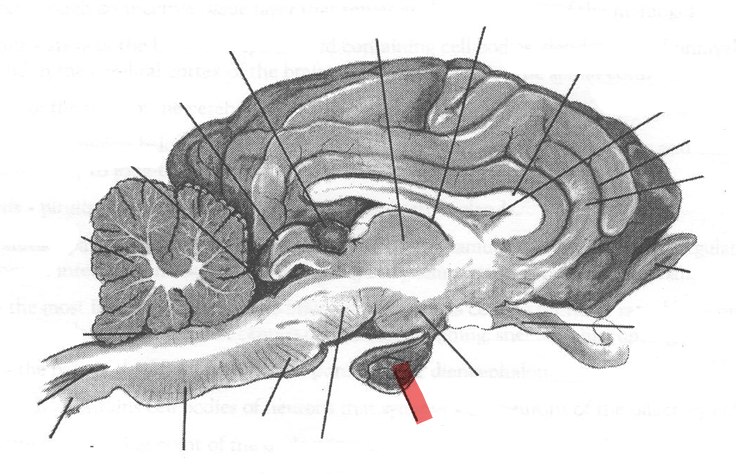

Identify highlighted arrow

Spinal cord

2

New cards

Identify highlighted arrow

Medulla

3

New cards

Identify highlighted arrow

Pons

4

New cards

Identify highlighted arrow

Midbrain

5

New cards

Identify highlighted arrow

Hypophysis

6

New cards

Identify highlighted arrow

Hypothalamus

7

New cards

Identify highlighted arrow

Optic nerve

8

New cards

Identify highlighted arrow

Olfactory bulb

9

New cards

Identify highlighted arrow

Gyrus

10

New cards

Identify highlighted arrow

Sulcus

11

New cards

Identify highlighted arrow

Corpus callosum

12

New cards

Identify highlighted arrow

Third ventricle

13

New cards

Identify highlighted arrow

Thalamus

14

New cards

Identify highlighted arrow

Pineal body

15

New cards

Identify highlighted arrow

cerebellum

16

New cards

Identify highlighted arrow

Fourth ventricle